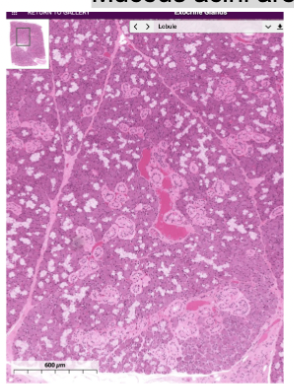

Kidney

Kidney:

Remove metabolic waste, foreign chemicals, regulate salt concentrations, and maintain blood volume and acid-base balance

Outer cortex

And inner medullary region

Renal pyramid, point/peak at renal papillae where urine drips out

Cortical tissue

Proximal distal convoluted tubules

Medullary rays and renal corpuscles